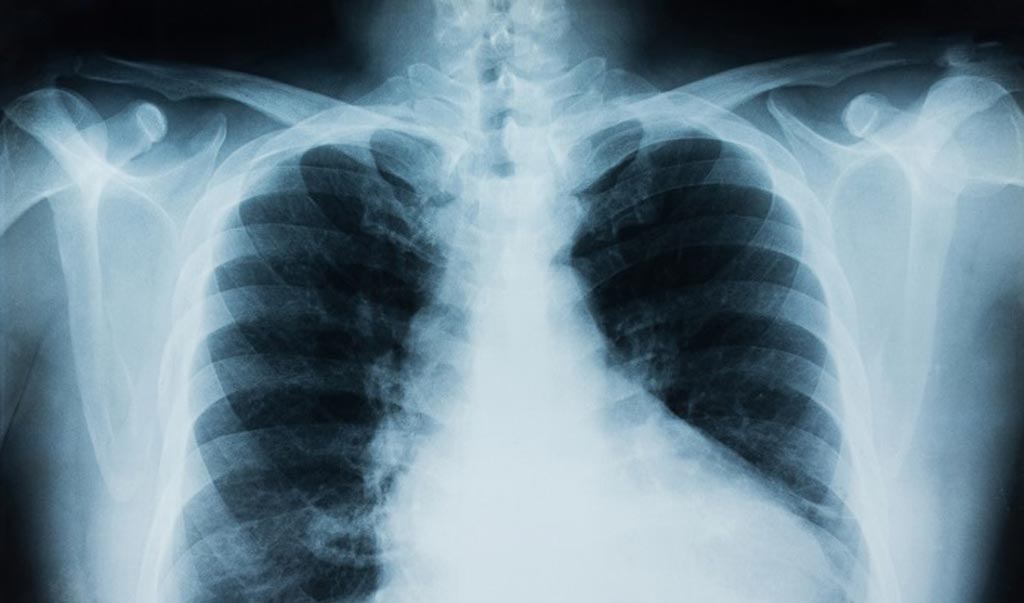

Rayos x de pulmones con covid. El tamano y el contorno del corazon. Pero cuando se realizan los rayos x del pecho mas del 50 de los afectados. Las radiografias de torax pueden mostrar cambios o problemas en los pulmones que derivan de problemas cardiacos.

Un impactante video difundido por la asociacion medica de rosario busca concientizar a la poblacion sobre el cuidado del coronavirus. Por ejemplo la presencia de liquido en los pulmones edema pulmonar puede ser el resultado de insuficiencia cardiaca congestiva. Las fotos de rayos x y tomografias computarizadas fueron captadas de un hombre chino de 44 anos que murio con coronavirus conocido como covid 19.

Los 4 tipos de pacientes con. Las imagenes de rayos x y las tomografias computarizadas de un hombre chino de 44 anos que murio de coronavirus muestran como la enfermedad devasta los pulmones de sus victimas. Si sufren un perjuicio severo puede.